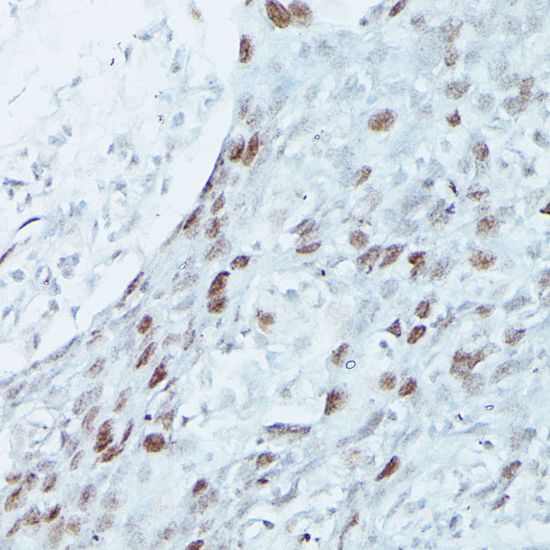

IHC-P analysis of human breast cancer tissue using GTX33312 MEF2C antibody.

Dilution : 1:100